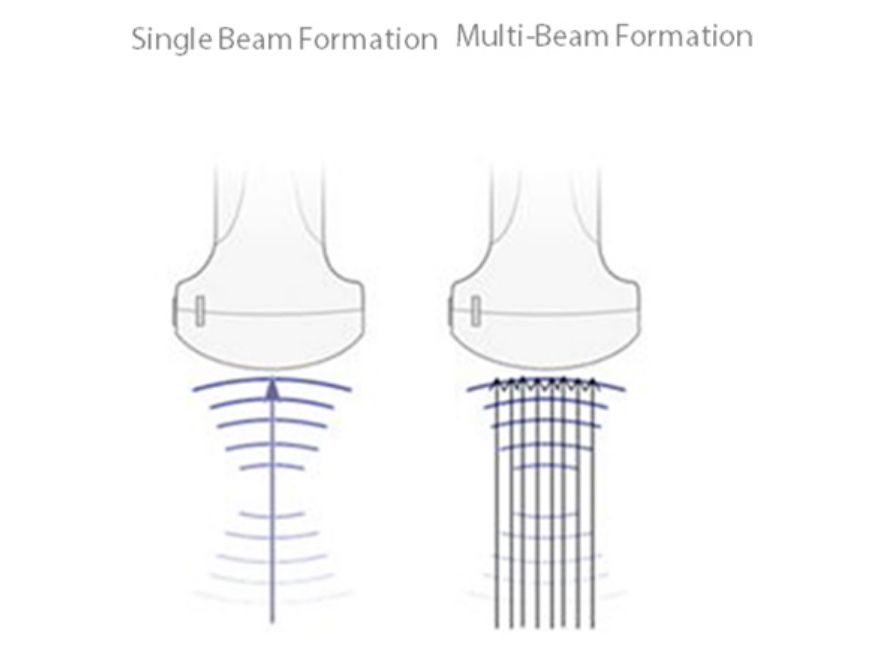

Maximum 8 times tasking for one transmitted beam, resulting in excellent time resolution and higher frame rate.